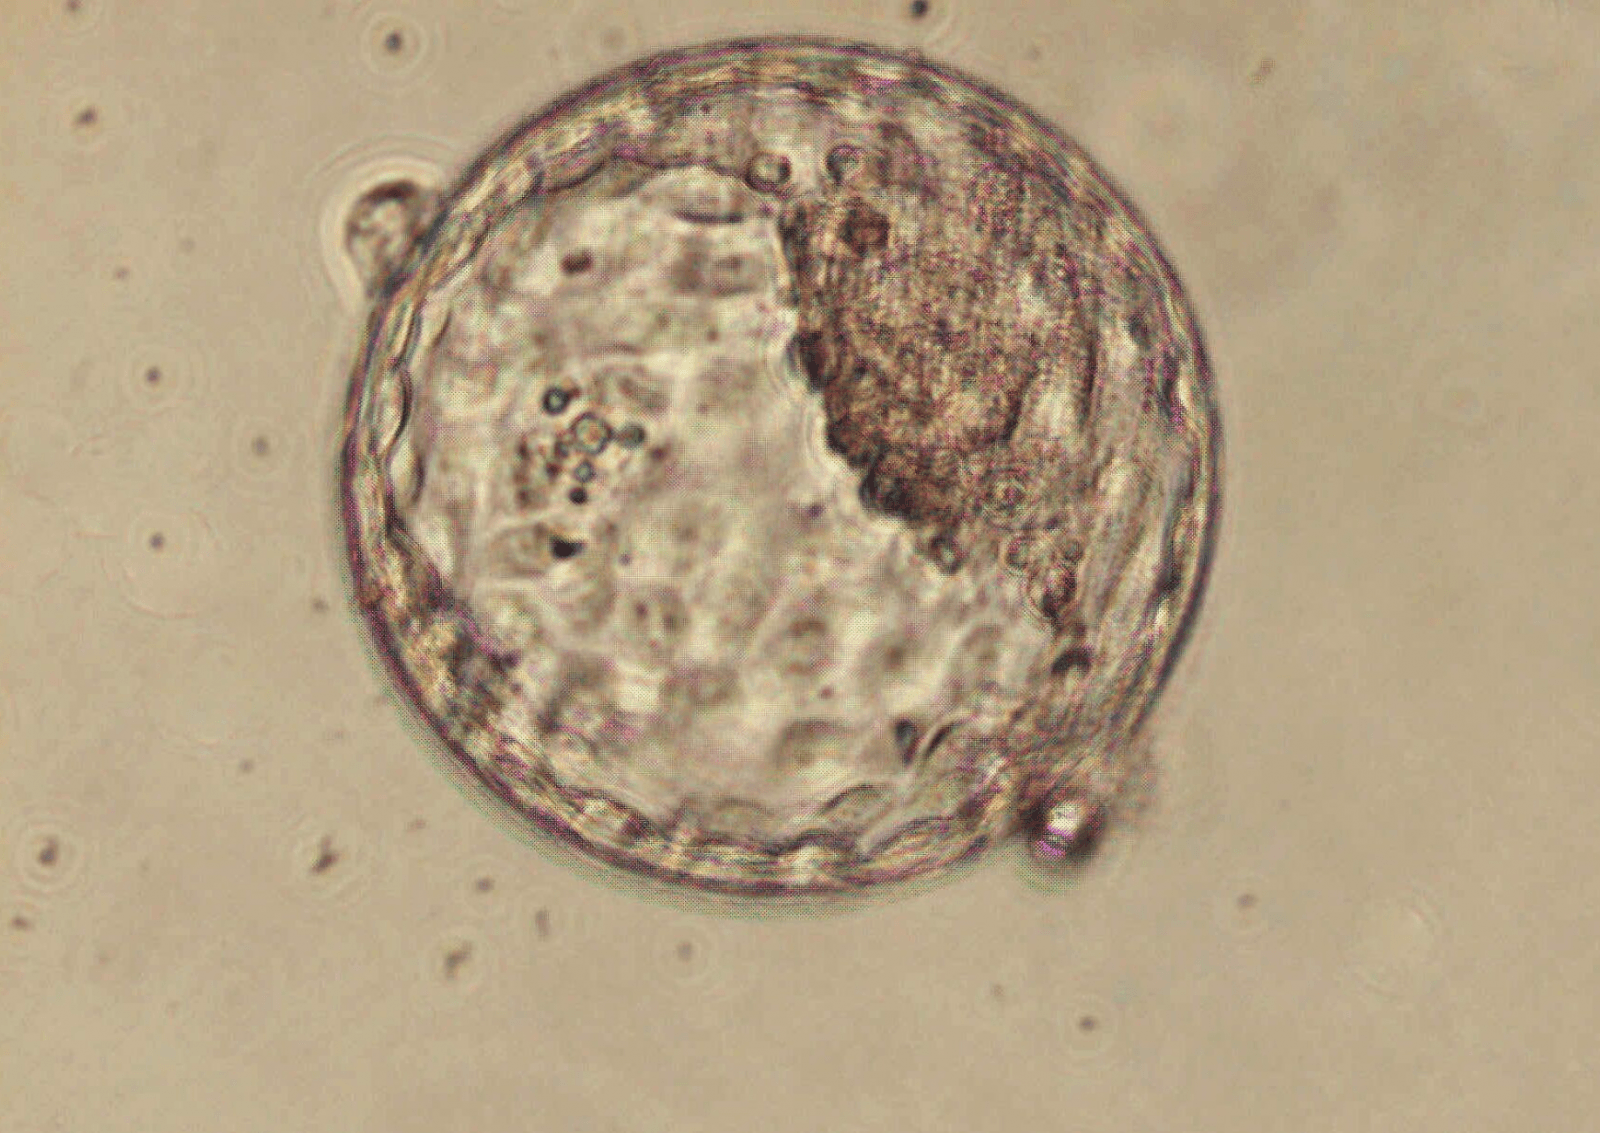

Struktury embriopodobne (blastoidy) wykazywały cechy podobne do tych przypisywanych zarodkom ok. 18-21 dni po zapłodnieniu. Miały morfologię podobną do naturalnych blastocyst (jedno ze stadiów rozwoju zarodkowego). Co ciekawe, blastoidy zaczęły tworzyć typy komórek, które prowadzą do wykształcenia tzw. listków zarodkowych. Wzorce ekspresji genów w blastoidach były podobne do komórek występujących w naturalnych blastocystach lub zarodkach po implantacji w macicy.

Najważniejszym etapem było przeniesienie struktur embriopodobnych do macic 8 samic. U 3 małp doszło do prawidłowej implantacji, co wywołało uwolnienie progesteronu i gonadotropiny kosmówkowej – głównych markerów rozwijającej się ciąży. Blastoidy wytworzyły także wczesny pęcherzyk ciążowy, czyli wypełniony płynem “worek”, który otacza rozwijający się zarodek i płyn owodniowy. I tu kluczowa adnotacja: blastoidy nie utworzyły zarodków i przestały się rozwijać po ok. tygodniu.